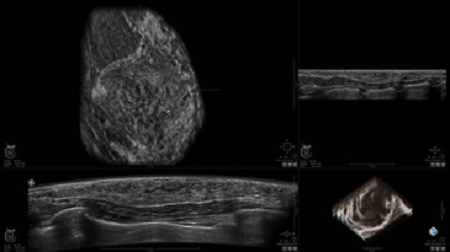

• Получение объемных 3D изображений с возможностью покадрового просмотра

• Получение изображений в поперечной плоскости (в реальном времени) и в коронарной плоскости (статическая, для указания нахождения соска)

• Отображение объемных 3D ультразвуковых изображений, которые состоят из традиционных поперечных и воссозданных коронарных и сагиттальных проекций

• Возможность отображения полного 3D изображения

• Стандартизованная ориентация изображения: «толстый срез» в коронарной плоскости; поперечная; сагиттальная плоскость; радиальный и антирадиальный поворот изображения; просмотр исключительно области интереса

• Изменяемая толщина среза: 0,5 - 10,0 мм (шаг 0,5 мм)

• Срез: 0,5 - 2,0 мм (шаг 0,5 мм)

• Одновременный просмотр двух изображений для сопоставления в коронарной плоскости